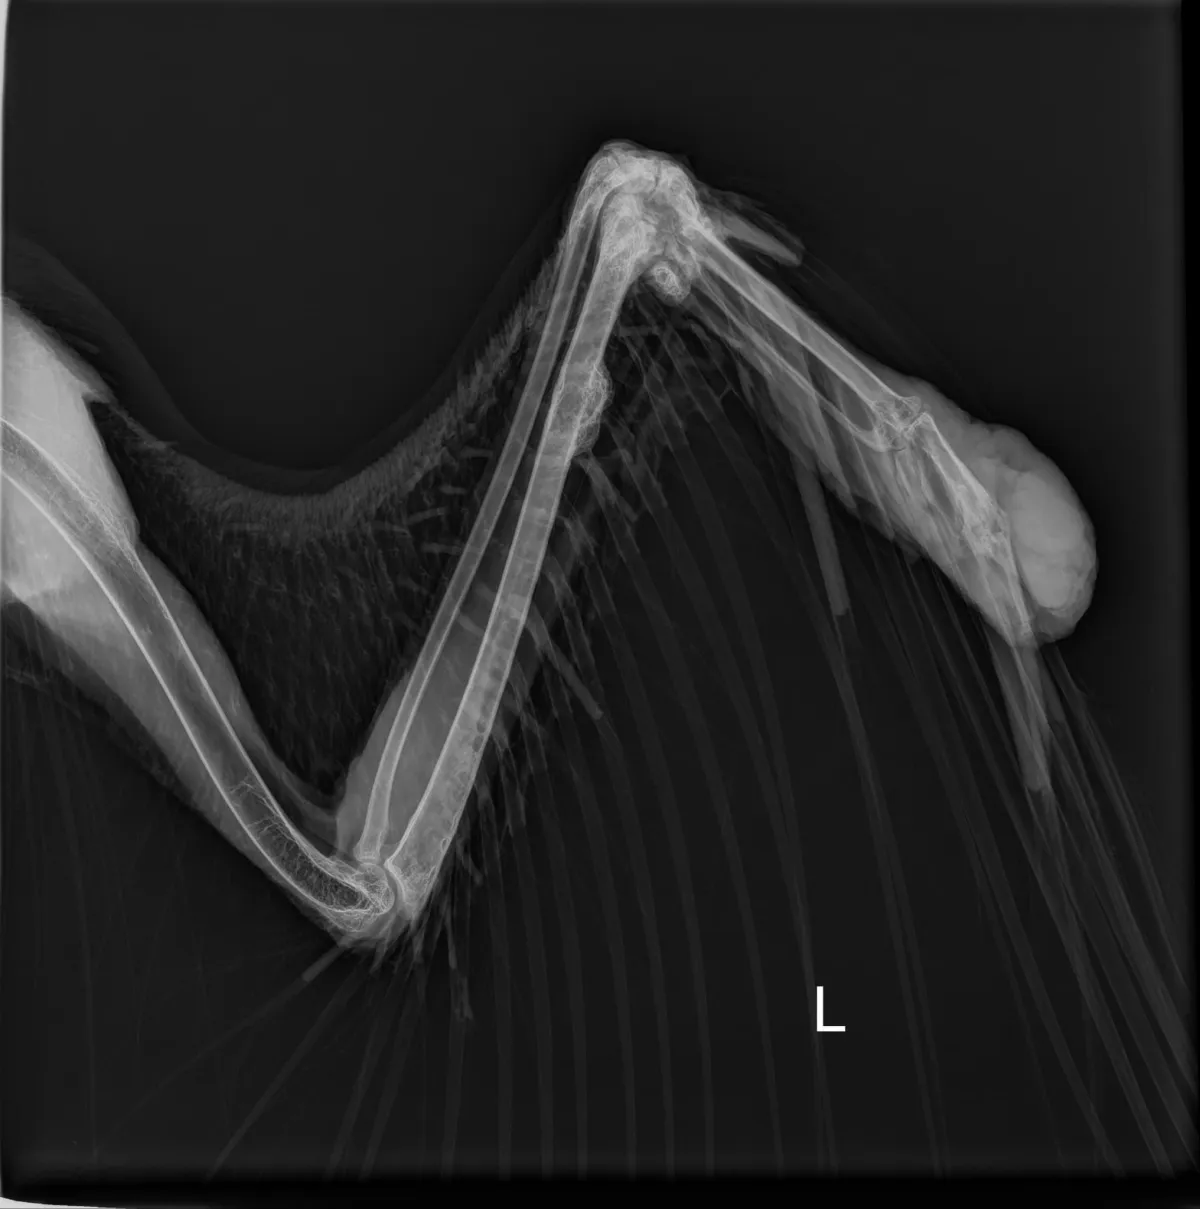

At first, Aurora was still able to participate in programs, but over time, the tumor began to interfere with her ability to comfortably extend her wing. It became clear that continuing in-person education wasn’t in her best interest.

Medical care – Ongoing check-ups and post-surgery recovery support.

Today, Aurora is healing beautifully in her aviary and adjusting well after her surgery.